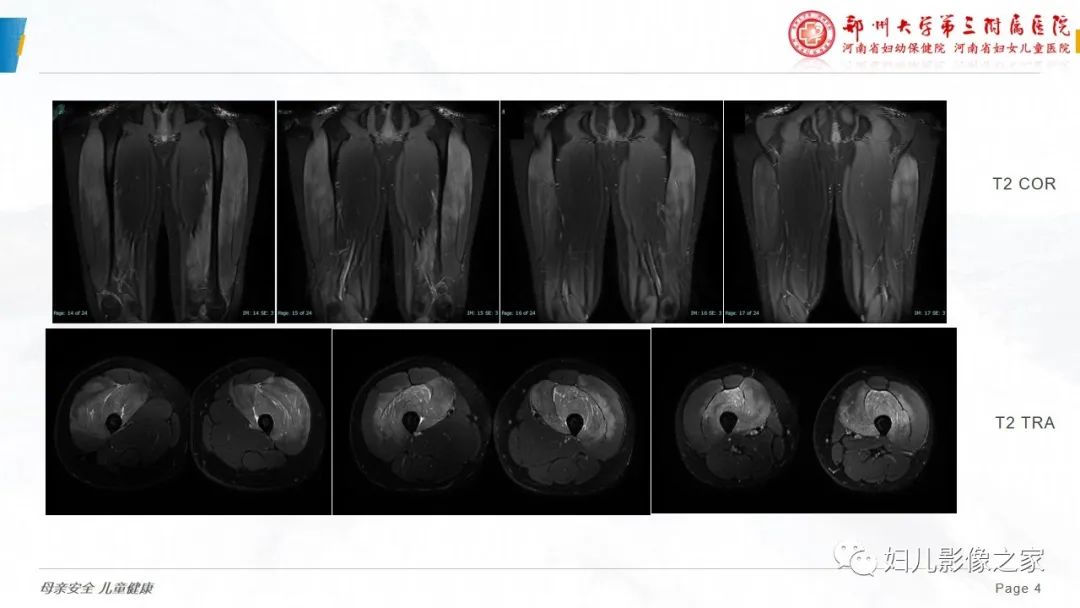

【病例】横纹肌溶解症1例MR影像-4